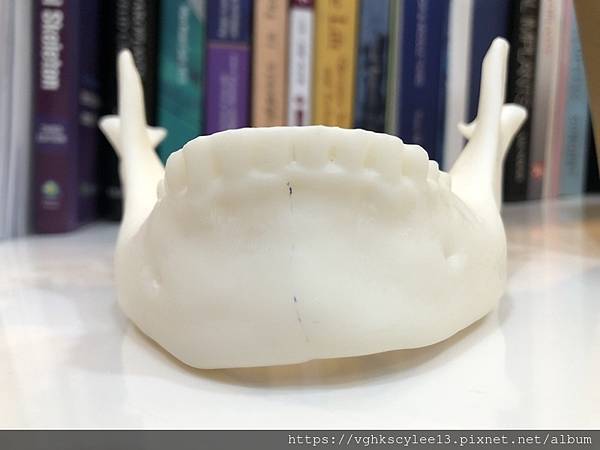

列印技術在美容醫學的運用:精準醫學

優點:1.克服目前成型假體的局限性,打造量身定制的專屬下巴。

2. 針對臉型不對稱或歪斜,外傷變形或手術後遺症的精準矯正,提升對稱性的治療。

下圖: 在李醫師確認後完美精準例印

窄小後縮的下巴,以精準3D列印技術來客製化醫師判斷後的外型下巴假體,一起改善嘴形相對的狀態。

窄小後縮的下巴,以精準3D列印技術來客製化醫師判斷後的外型下巴假體,一起改善嘴形相對的狀態。

3D模擬後 列印出吻合的設計下巴假體

下圖:或是以3D列印導板客製化下巴假體,以goretex材料按下巴導板來雕刻適合的形狀來訂製下巴,必要時把不規則的或不對稱骨頭磨平來改變術前傾斜。